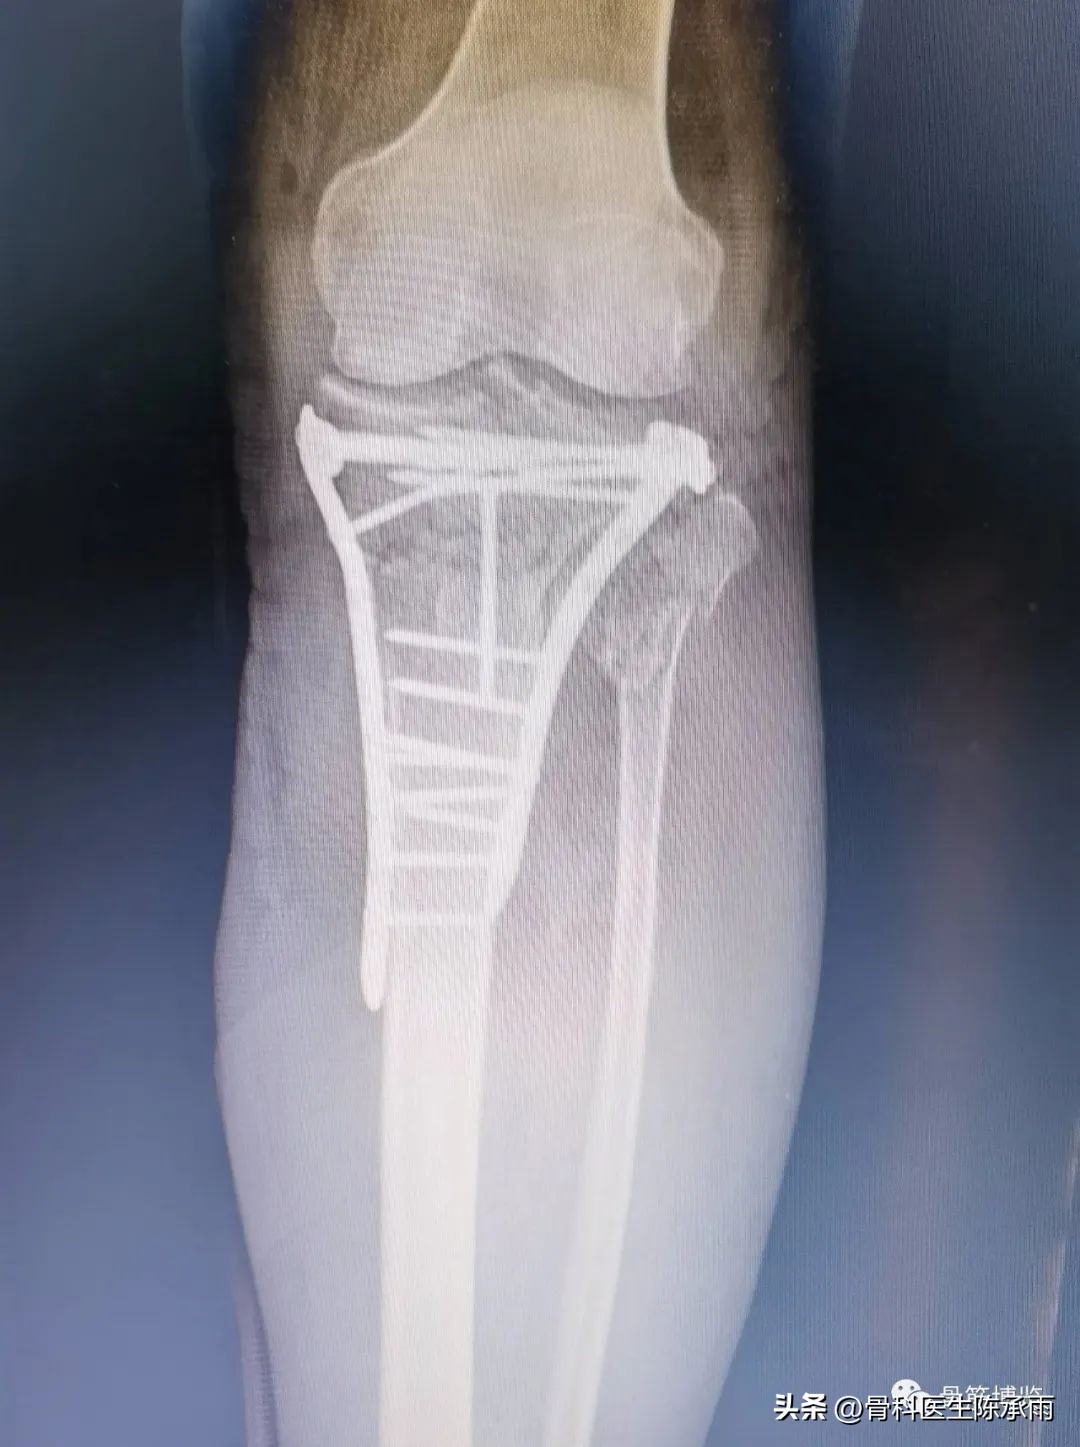

1例

2例

3例

4例

5例

6例

7例